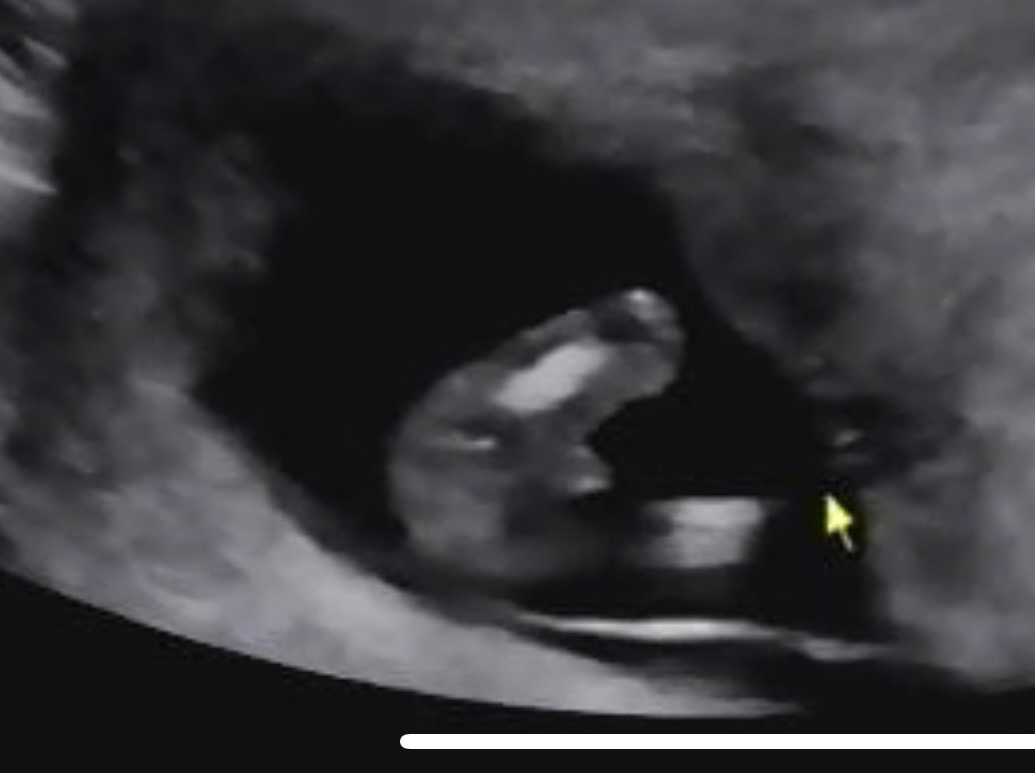

12주!!!! 초음파 잘 보시는 분!!!

초음파 보러갔다가 다리사이 무언가를 보았는데 들어갈 수 있을까요....?

12주말고 16주까지 두고 보세요 ! 딸을 원하시나봐요